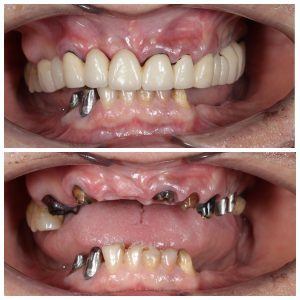

Вот один из примеров

Пациентка достаточно трепетно относится к зубам. Как мы видим, она активно занималась лечением и восстановлением зубов. Но время идет, а следовательно, срок службы пломб, коронок и мостов подошел к концу. Кроме того, что портятся свои зубы, проблемы могут начаться и с установленными имплантатами, как в данном случае. Вторые также приходится удалять. Не говоря уже о том, что некоторые доктора до сих пор устанавливают пластиночные имплантаты без каких-либо показаний. Которые очень легко могут сломаться, как в данном случае. А все почему? Да потому, что не было комплексного подхода, плана лечения и видения ситуации. Вот скажите, зачем сюда «впихнули» тонкую пластину при такой ширине кости? А ведь наверняка перед операцией условия были еще лучше. Ну уж не хуже то точно.

До и после удаления